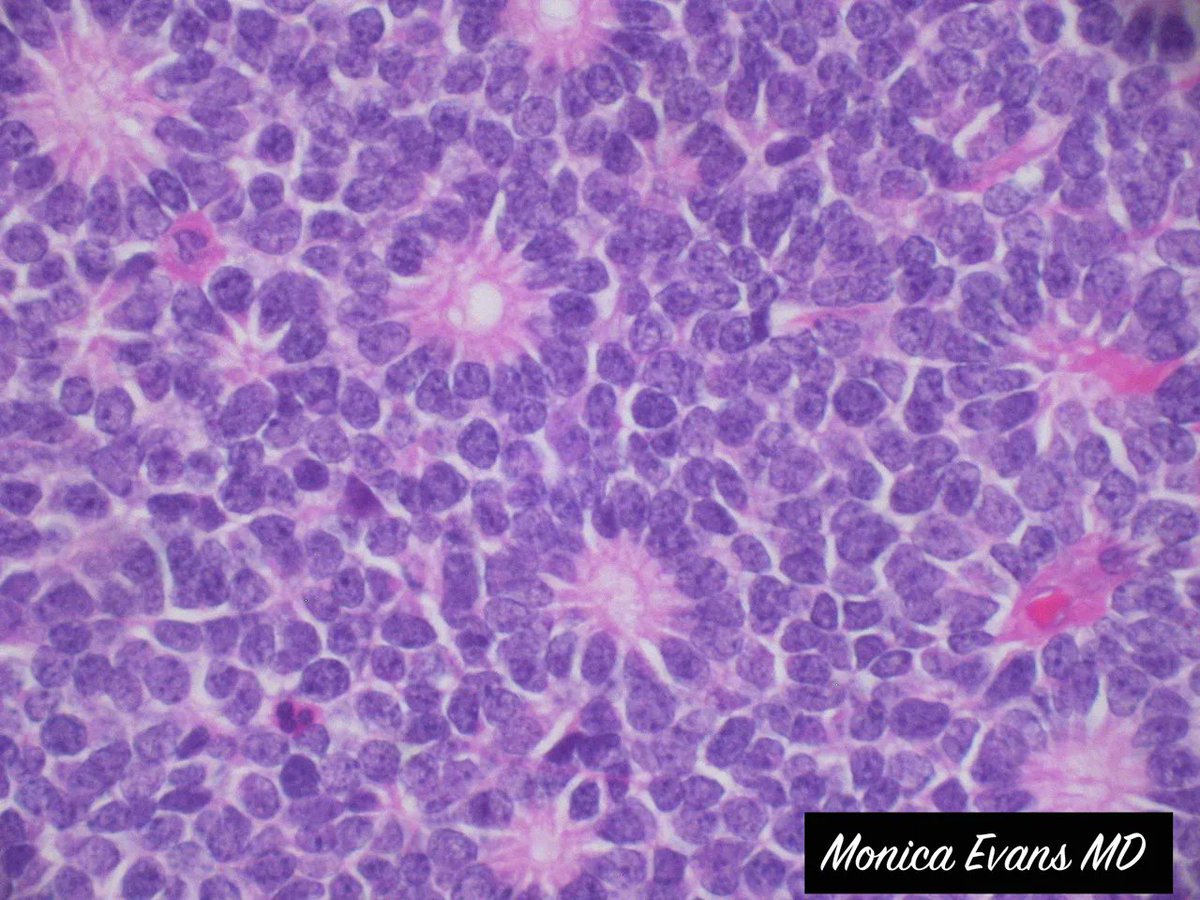

Ulcerated Anal Amelanotic Melanoma in 60y/M. #APCON2022 #APCON2022PathTweet GI James Padma Priya J Kenny De Gracia T. Archana bhat Aditya Agnihotri 🇮🇳 Vijay Shankar S Annie A. Wu, MD, PhD Olaleke Folaranmi Daisy Maharjan Dante Aswathy Menon Ananthvikas Dr Anila Sharma Frank Ingram, MD Arunima Deb, MD #pathology #PathTwitter